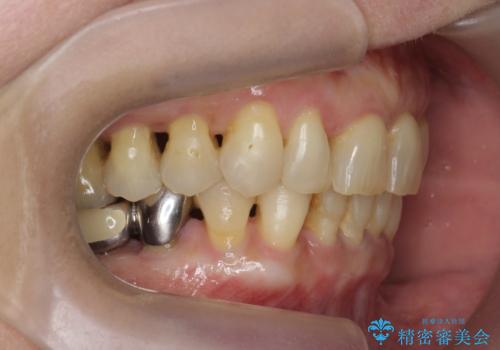

前歯のすれ違いによる歯周病を矯正治療で改善

- 下顎前歯のグラつきがどんどん悪くなり、痛くて噛めなくなってきたことの改善を希望され来院されました。

下顎前歯の1本は前歯よりも前に出てしまい後ろからの力を受けることで、周囲の骨も吸収しグラつきも大きくみられます。

通常 抜歯後はインプラントやブリッジといった方法で欠損部位の機能や審美性を回復しますが、今回は臨在する歯のガタつきも利用し上下の歯を矯正治療することで人工物を装着することなく歯を並べます。